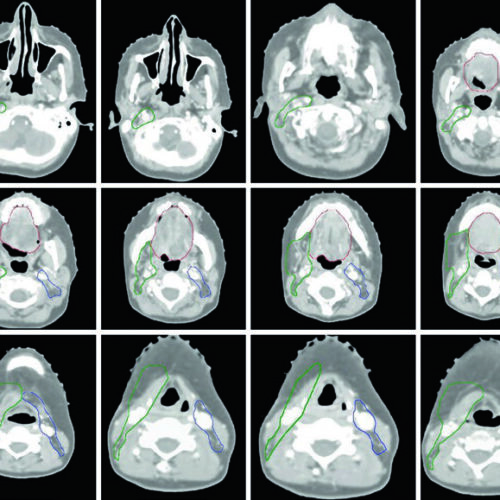

Delineamento de volumes-alvo e OAR em tumores de cabeça e pescoço: nasofaringe, orofaringe, laringe, hipofaringe, cavidade oral, seios paranasais, glândulas salivares e tireoide.